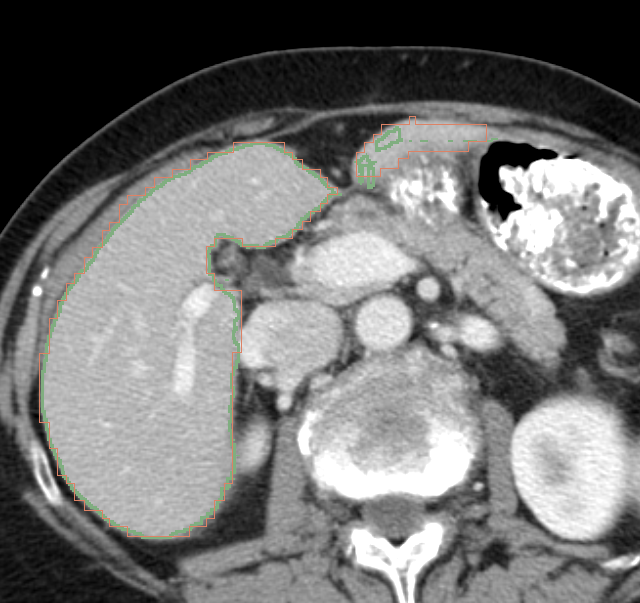

在 3D Slicer 中完成了完整流程:

- 导入CT数据 + AI分割结果(TotalSegmentator)

- 使用 Segment Editor 进行基础修正(Scissors / Paint)

- 与官方标注进行叠加对比(颜色区分 + 透明度控制)

在对比过程中,识别出AI的典型误差模式:

- 细长结构(如边缘延伸)容易漏分

- 邻近结构(如胆囊)边界处理粗糙

- 层间连续性不稳定(出现断层)

- 边界判断更偏“灰度”,而非“解剖规则”

同时理解到:

医学分割的边界并不完全依赖灰度,而是遵循“统一标注规则(outer contour)”

例如:

- 下腔静脉贴近肝脏时,答案会整体包裹

- 表面凹陷区域会被“平滑处理”